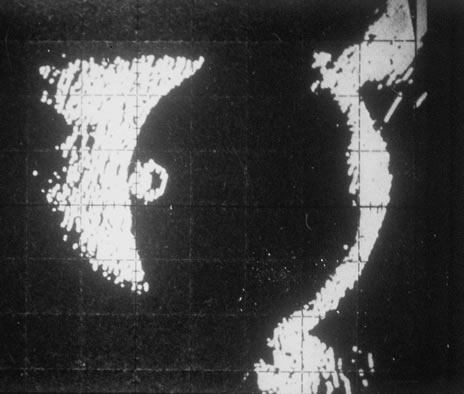

In primary ocular HSV infections, a severe follicular conjunctivitis with regional adenopathy is present. Vesicles may appear on the eyelid skin or lid margin, producing blepharitis (Fig. 3). Corneal involvement initially takes the form of a superficial punctate keratitis, which may progress to dendritic or geographic ulceration. Stromal infiltrates and uveitis are less common and relatively mild in primary disease. In uncomplicated cases, lesions usually heal completely in 2 to 3 weeks without scarring. Most cases of ocular HSV are recurrences. Recrudescent ocular herpes may take the form of dendritic or geographic ulcers, recurrent erosions, interstitial or disciform stromal keratitis, and anterior uveitis.3 HSV may also be an agent of retinitis and acute retinal necrosis (Fig. 4).

The acute retinal necrosis (ARN) syndrome is most often caused by the herpes zoster virus, although occasionally it may be a result of herpes simplex infection.12 It is typically described in healthy patients although association with immunosuppressed patients has also been described. Granular, nonhemorrhagic areas of retinal necrosis may be observed in the fundus, often rapidly coalescing with resulting blindness often caused by retinal detachment. There is often an associated vasculitis and vitritis. In immunocompromised patients VZV or HSV retinitis may also take the pattern of progressive outer retinal necrosis (PORN) (Fig. 6). PORN differs from ARN in that the former is multifocal, localized to the outer retina, and is less often associated with vasculitis and vitritis.